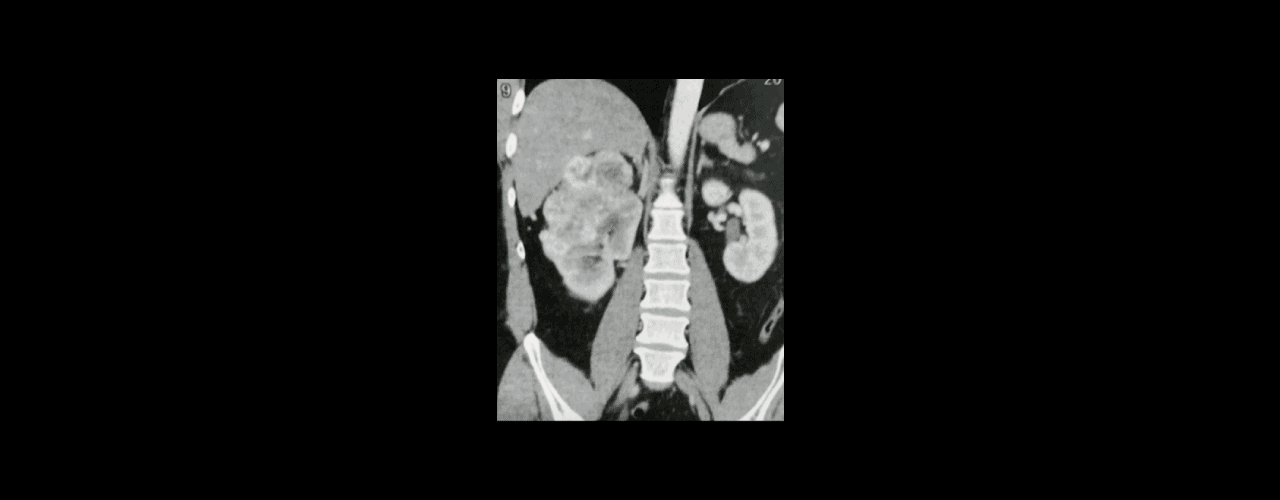

Atualmente, cerca de 65% dos pacientes com Câncer de Rim têm sido diagnosticados como doença localizada. Isso é uma consequência da utilização em larga escala dos exames de imagem.

Em sua maioria, os pacientes identificam nódulos renais suspeitos em exames de rotina ou realizados para avaliar outros problemas de saúde.